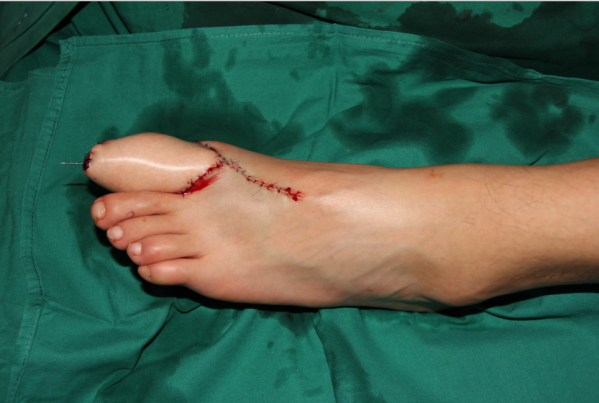

术后即刻

术后12天,没有感染